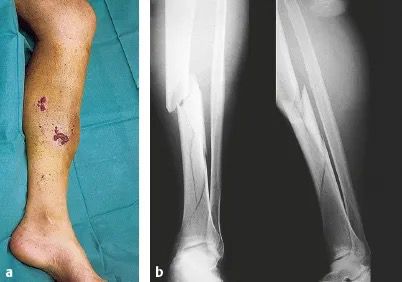

Q.14. What's the finding?

Correct Answer : D